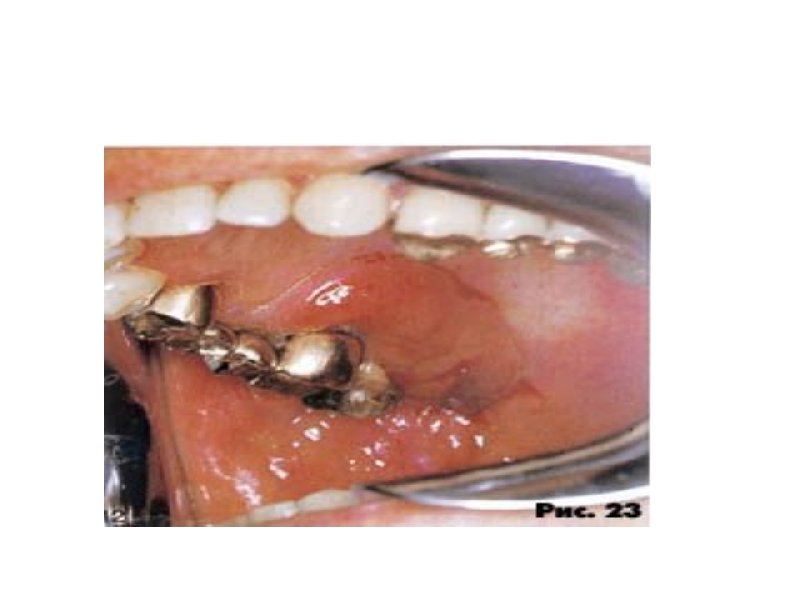

Наружные лимфоузлы при неходжкинских лимфомах